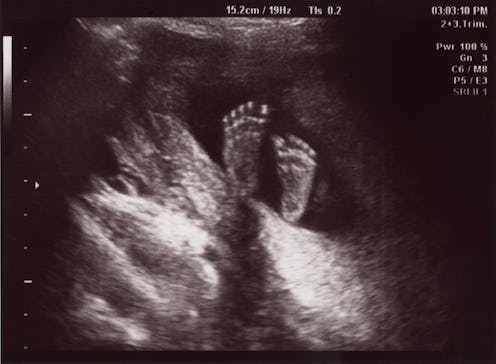

It's somewhat surprising that in our high-tech world, we still can't figure out how big a baby is. And it turns out that the higher-tech the method of estimating the baby's size is, the less accurate the results tend to be. Ultrasound images are off by an average of between 11.6 to 19.4 ounces, according to a 2001 University of Michigan Medical School study, while determining fetal size by the old-fashioned method of feeling the mother's stomach produces estimates that are off by an average of 11.6 ounces.

Scary as the word "macrosomia" may sound, a full 15 percent of babies weigh more than 8 lbs., 13 oz. at birth, according to a 2013 Harvard study, so macrosomia is actually totally and completely normal. Still, hearing those words "big baby" might put an expectant mom in a frame of mind that puts a new spin on the word "expecting" and makes her feel a bit like this little guy here: